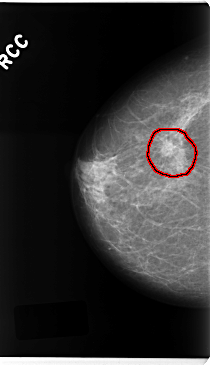

C_0225_1.RIGHT_CC

RIGHT_CC LINES 4736 PIXELS_PER_LINE 2728 BITS_PER_PIXEL 12 RESOLUTION 50 OVERLAY

FILE: C_0225_1.RIGHT_CC.OVERLAY

TOTAL_ABNORMALITIES 1

ABNORMALITY 1

LESION_TYPE MASS SHAPE OVAL MARGINS SPICULATED

ASSESSMENT 5

SUBTLETY 5

PATHOLOGY MALIGNANT

TOTAL_OUTLINES 1

BOUNDARY